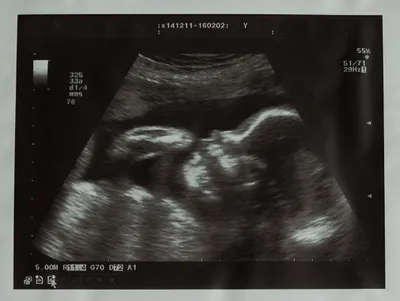

2Dエコーは平面(縦と横の情報)で見る超音波の画像で、おなかの赤ちゃんの体の断面が映し出されます。

おなかの赤ちゃんの内臓など、体の内部の様子も観察できる方法です。

妊娠経過や赤ちゃんに異常がないかを確認するための情報は、条件の制約が少なく4Dエコーより得やすいのが特徴です。

普段の妊婦健診では2Dエコー検査

一般的な妊婦健診では2Dエコー検査を行います。

立体像でなく断面像なのでママやパパにとってはわかりづらいかもしれませんが、おなかの赤ちゃんの発育や健康、羊水や胎盤などの異常などをチェックするために重要な検査です。